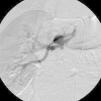

Non-invasive 24-hour blood pressure monitoring revealed stage I hypertension (mean daytime blood pressure 156/87mmHg). Hormonal and imaging studies were also performed for etiologic diagnosis of his hypertension, as well as a captopril test, which was positive for renovascular hypertension. Following this result, renal angiography was performed, which revealed, bilaterally, two renal arteries, and in addition, to the right, depending on the superior artery, three saccular aneurysms 14mm, 6mm and 3.5mm in size. The largest aneurysm appeared to compress the lower polar artery (Figure 1). The aneurysms were treated with placement of a polytetrafluoroethylene (PTFE)-coated stent, in order to prevent expansion and rupture of the aneurysms and to treat the hypertension. Digital subtraction angiography was performed using a right femoral approach. A 65cm 4F sheath was introduced, and the right renal artery was engaged with a 4F Cobra catheter and a 0.014-inch hydrophilic guidewire. Aneurysm morphology was assessed using conventional angiography and flat-panel computed tomography. Stent diameter and length were determined from a three-dimensional flat-panel rotational angiography data set. After administration of 5000 IU of heparin, the aneurysm was crossed with the guidewire and catheter. The wire was exchanged through the same catheter with a 0.014-inch guidewire. Finally, a 6×22-mm covered Atrium stent was deployed, bridging the aneurysm and covering the artery, resulting in successful exclusion of the aneurysms (Figures 2 and 3). The patient was admitted the day before the procedure and was discharged the day after, medicated with 100mg aspirin and 75mg clopidogrel/day, as dual antiplatelet therapy. Ten months after the procedure the patient was asymptomatic, with normal blood pressure and without antihypertensive therapy.